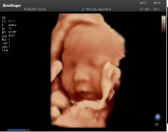

4容積探頭

積探頭是在二維圖像的基礎(chǔ)上,將連續(xù)采集的空間分布位置,經(jīng)過計算機重建算法,從而獲得完整的空間形態(tài)。

適用于:胎兒面部、脊柱和肢體等。

優(yōu)勢特點:快速獲取、掃查連續(xù)均勻、解剖結(jié)構(gòu)顯示為容積數(shù)據(jù)、準確進行容積測量。